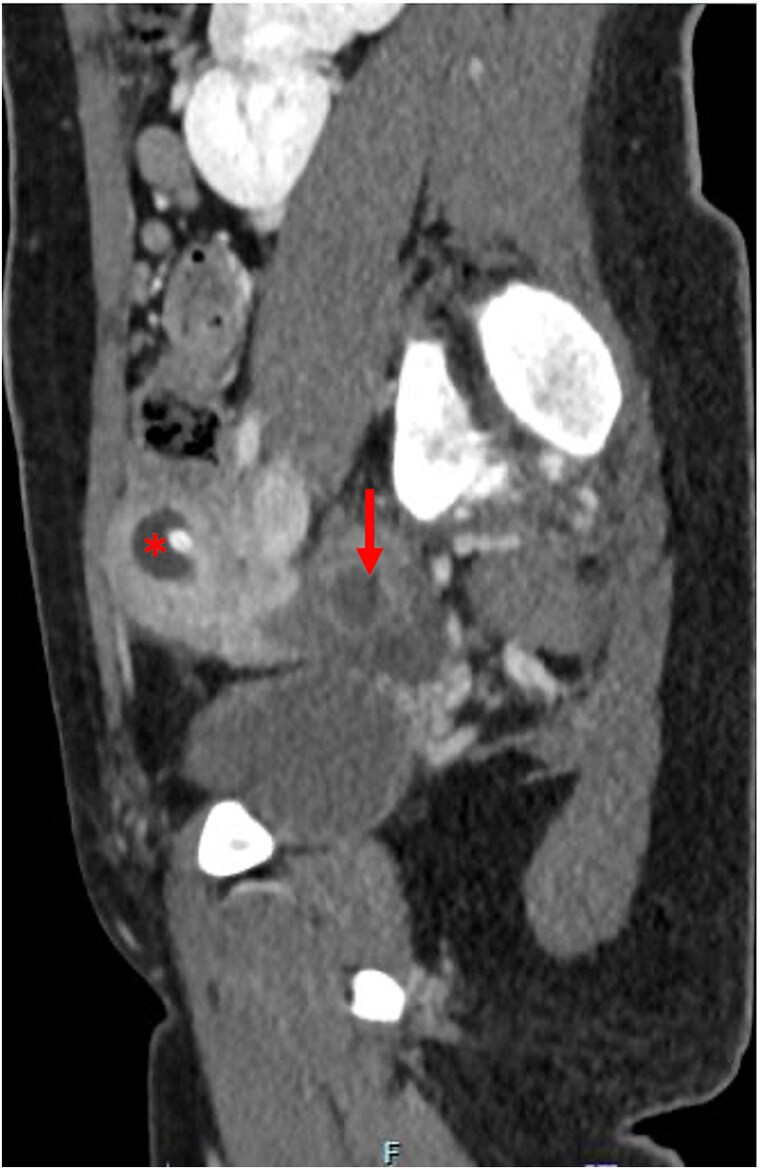

MRKH综合征(mayer - rokitansky - k - hauser综合征)是一种生殖道畸形,发生率约为5000分之一。其特点是先天性发育不全或明显的苗勒管衍生结构发育不全。大约3%的MRKH患者有正常的子宫。一名12岁健康女性,表现为持续周期性严重右下腹疼痛。她被发现有MRKH综合征,右侧子宫功能正常,有子宫积血和同侧输卵管积血。随后,她接受了诊断性膀胱镜检查、阴道镜检查和盆腔腹腔镜检查。腹腔镜下行子宫积血、输卵管积血引流,子宫造口置管及子宫前腹壁固定。术后症状完全消失。2周后的计算机断层扫描显示血肿消退,输卵管积血明显改善。子宫功能正常的MRKH综合征可能表现为青春期女性患者的周期性腹痛。腹腔镜子宫引流放置是一种治疗选择。

Mayer-Rokitansky-Küster-Hauser (MRKH) syndrome is a reproductive tract malformation occurring in ~1 in 5000 female births. It is characterized by congenital agenesis or marked hypoplasia of the Mullerian ducts derivative structures. About 3% of MRKH patients have a functioning uterus. A 12-year-old otherwise healthy female presented with persistent cyclic severe right lower quadrant pain. She was found to have MRKH syndrome with a right-sided functioning uterus and hematometra and ipsilateral hematosalpinx. She subsequently underwent diagnostic cystoscopy, vaginoscopy, and pelvic laparoscopy. Laparoscopic drainage of the hematometra and hematosalpinx, and hysterostomy catheter placement and uterine fixation to anterior abdominal wall were performed. Symptoms fully resolved post-operatively. A computed tomography scan 2 weeks later demonstrated resolution of the hematometra and significant improvement in the hematosalpinx. MRKH syndrome with a functioning uterus may present as cyclic abdominal pain in adolescent female patients. Laparoscopic uterine drain placement is a management option.